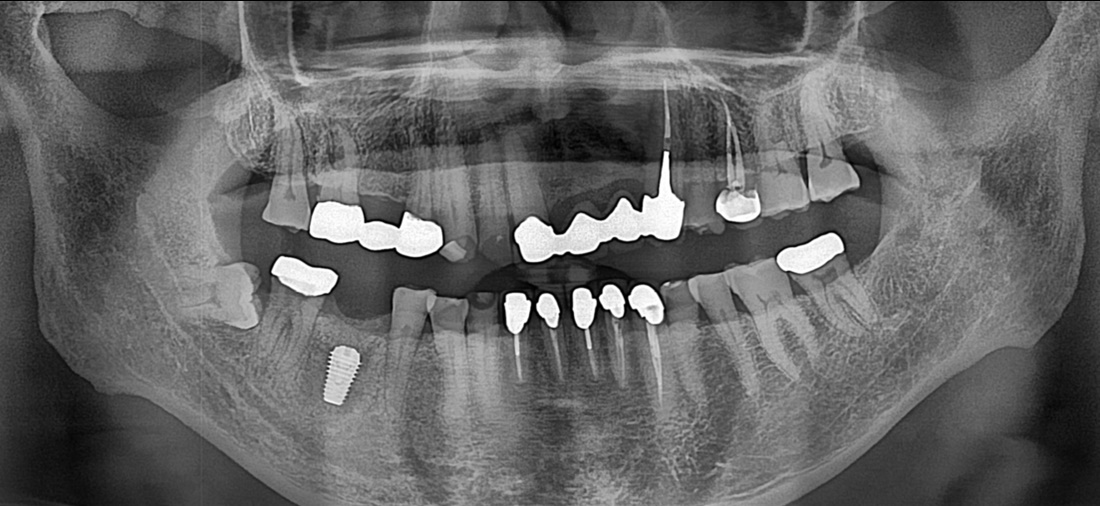

발치 후 치조골 이식

발치 부위 이식된 인공 뼈가 단단해진 후 임플란트 식립을 진행하였습니다.